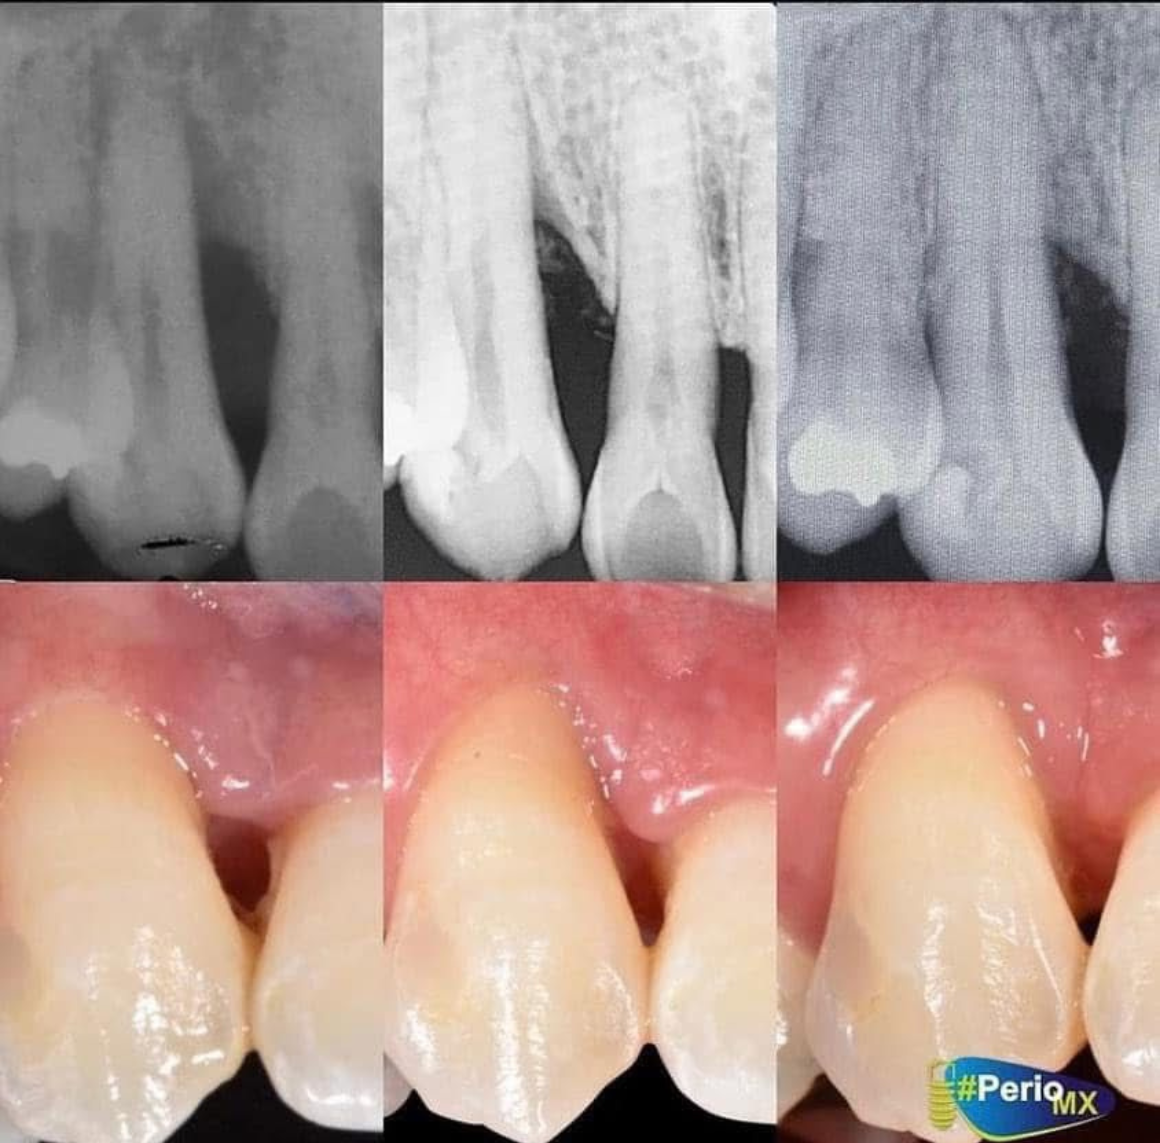

Queremos darte lo mejor de lo mejor por parte de PerioMx, donde encontraras muchos cursos de nivel alto para especialistas en periodoncia, entrevistas exclusivas, webinars, podcast, entre muchas otras cosas no dudes en descargar la primer applicación en el area de periodoncia.

Contenido producido por profesionales y expertos en el area de periodoncia.